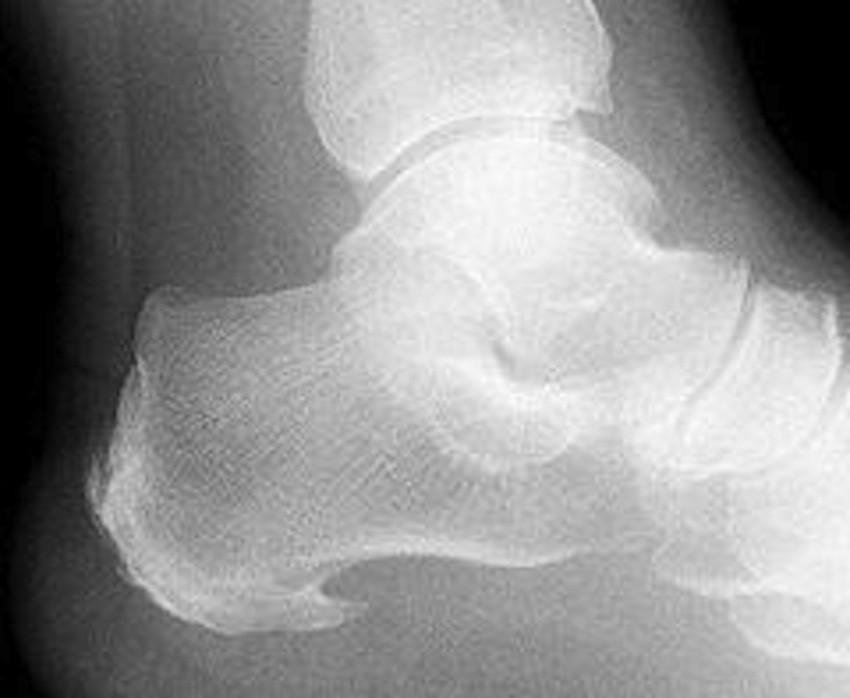

Zwyrodnienie kości piętowej powstaje najczęściej w wyniku intensywnego obciążania stopy lub w następstwie nieprawidłowo wyleczonej kontuzji. Dodatkowymi czynnikami mogą być też nadwaga, podeszły wiek lub nieprawidłowo dobrane obuwie. Deformacja diagnozowana jest zazwyczaj już podczas wywiadu z pacjentem i potwierdzana w oparciu o zdjęcie RTG stopy. Ortopeda może zalecić różne sposoby leczenia zwyrodnienia, w zależności od stopnia jego zaawansowania. W najlżejszych przypadkach można je zacząć od noszenia specjalnego obuwia, amortyzującego stopę w trakcie chodzenia lub korzystania z wkładek, które odciążają piętę. Są to jednak sposoby, które pomagają jedynie w wypadku pacjentów, u których zwyrodnienie nie jest jeszcze zaawansowane.